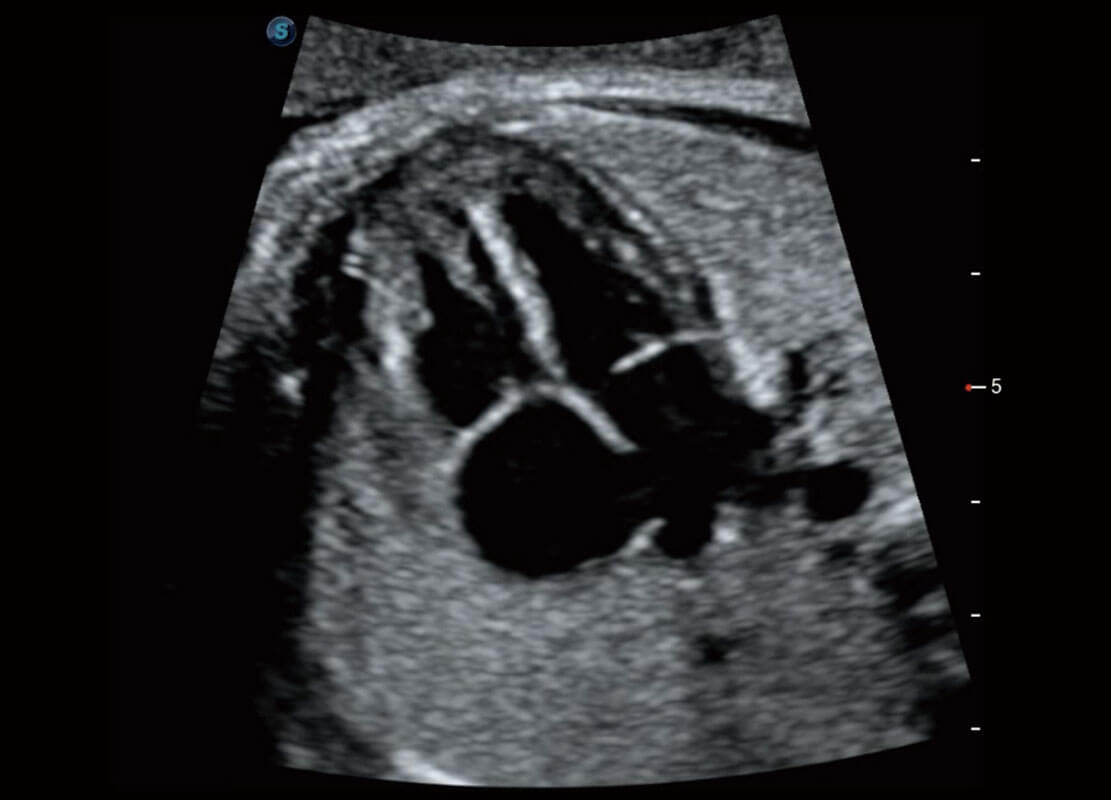

P60搭载一系列胎儿心脏成像技术,实现精细的胎儿心脏评估。

• 四腔切面

• 右室双出口